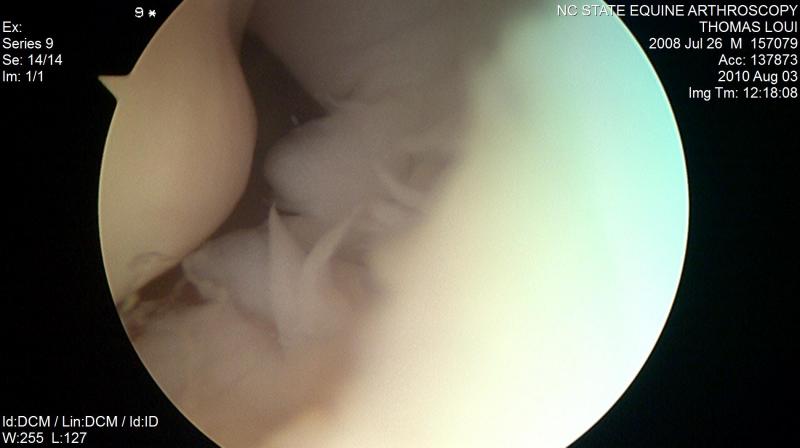

En esta actividad se presentara una imagen de la articulación metacarpofalángica de los equinos y en ella deberás señalar el elemento que se te indique

1 superficie articular distal del tercer metacarpiano 2 membrana sinovial 3 Espacio interarticular

4 articulación metacarpofalángica

5 generalidades articulación metacarpofalángica 6 generalidades articulación metacarpofalángica